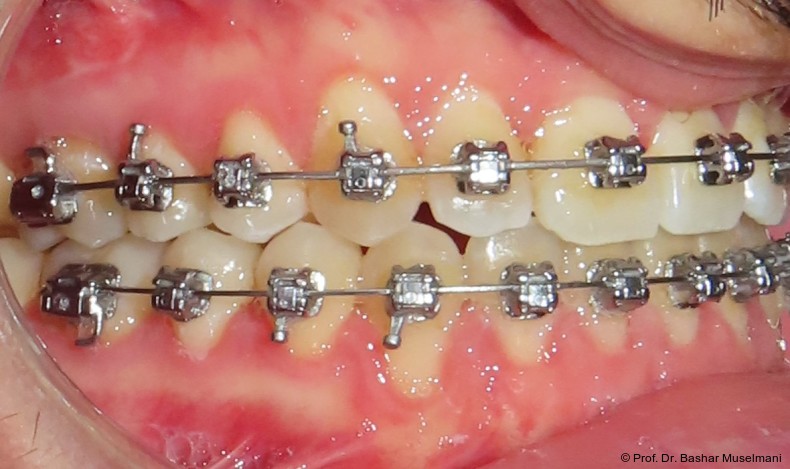

Bogensequenz und mechanische Umsetzung

Der Bogenwechsel erfolgte in einem standardisierten Intervall von acht Wochen. Die Sequenz war in beiden Kiefern weitgehend identisch und wie folgt aufgebaut:

• 0.013" CuNiTi (OK / UK)

• 0.016" CuNiTi (OK / UK)

• 0.018" CuNiTi (OK / UK)

• 0.014 x 0.0275" CuNiTi (OK / UK)

• 0.016 x 0.0275" Edelstahl (OK)

• 0.018 x 0.0275" CuNiTi (OK / UK)

• Abschlussbogen: 0.018 x 0.0275" TMA (OK/UK)

Diese Sequenz ermöglichte eine schrittweise Ausformung der Zahnbögen, eine kontrollierte Torque-Expression sowie eine präzise Feineinstellung in der Abschlussphase (Abb. 5a–e).